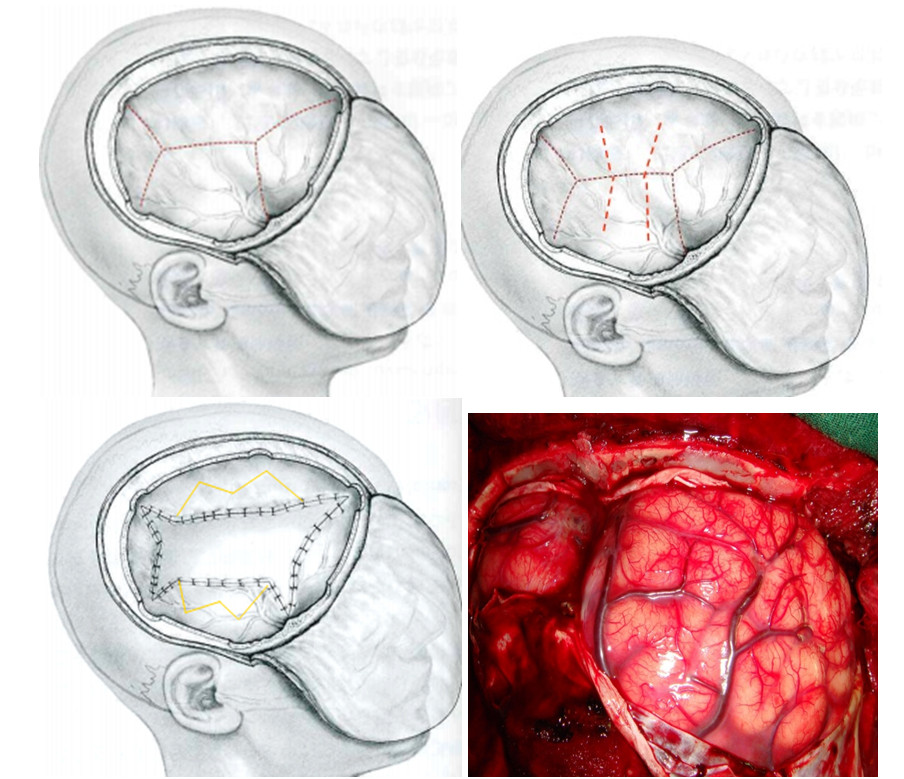

Hubet5555 chuẩn mã hóa SSL quốc tế khi có chỉ định Hubet8888 lì xì hội viên mới mở sọ giảm áp, thân nhân sẽ được tư vấn đầy đủ về những rủi ro cũng như lợi ích mang lại. Khi có sự đồng ý của gia đình, Hubet8888 lì xì hội viên mới viên sẽ mổ lấy bỏ đi một phần xương sọ đủ lớn để tổ chức não bị phù nề có không gian thoát ra ngoài, giảm áp lực nội sọ. Qua đó, làm tăng áp lực tưới máu não, làm giảm tổn thương do tăng áp lực nội sọ. Phần xương sọ lấy bỏ sẽ được bảo quản tại ngân hàng mô, viện Bỏng quốc gia. Sau 1-3 tháng, nếu tình trạng Tại game HUBET cho phép sẽ Hubet8888 lì xì hội viên mới đặt lại bản xương sọ.